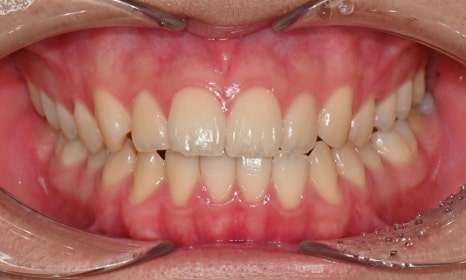

치료 전후 비교 - 연세정원치과

약 1년 간의 교정 치료를 통해 어긋나 있던 치아 중심선이 자연스럽게 맞춰졌고, 중심선 비대칭이 개선 및 하악 아랫입술 돌출도 눈에 띄게 호전되었습니다. 무엇보다 치료 기간 동안 앞니의 치근 흡수는 추가적인 진행 없이 안정적으로 유지되었습니다.

돌출을 조금 더 개선하는 것을 추천했으나, 환자가 갑자기 군 입대를 하게 되어 현 상태로 치료를 마무리하기로 하였습니다. 치료 전후 치아 위아래 중심선이 일치하며 좌우 어금니 교합도 향상되었습니다. 하악 치열의 후방 이동으로 아래 입술의 돌출도도 많이 개선되었습니다. 멀리서도 믿고 내원해주고, 치료 기간 동안 성실히 협조해준 환자분께 감사드리며 앞으로도 건강한 치아로 군 생활 잘 마치길 응원합니다 :)